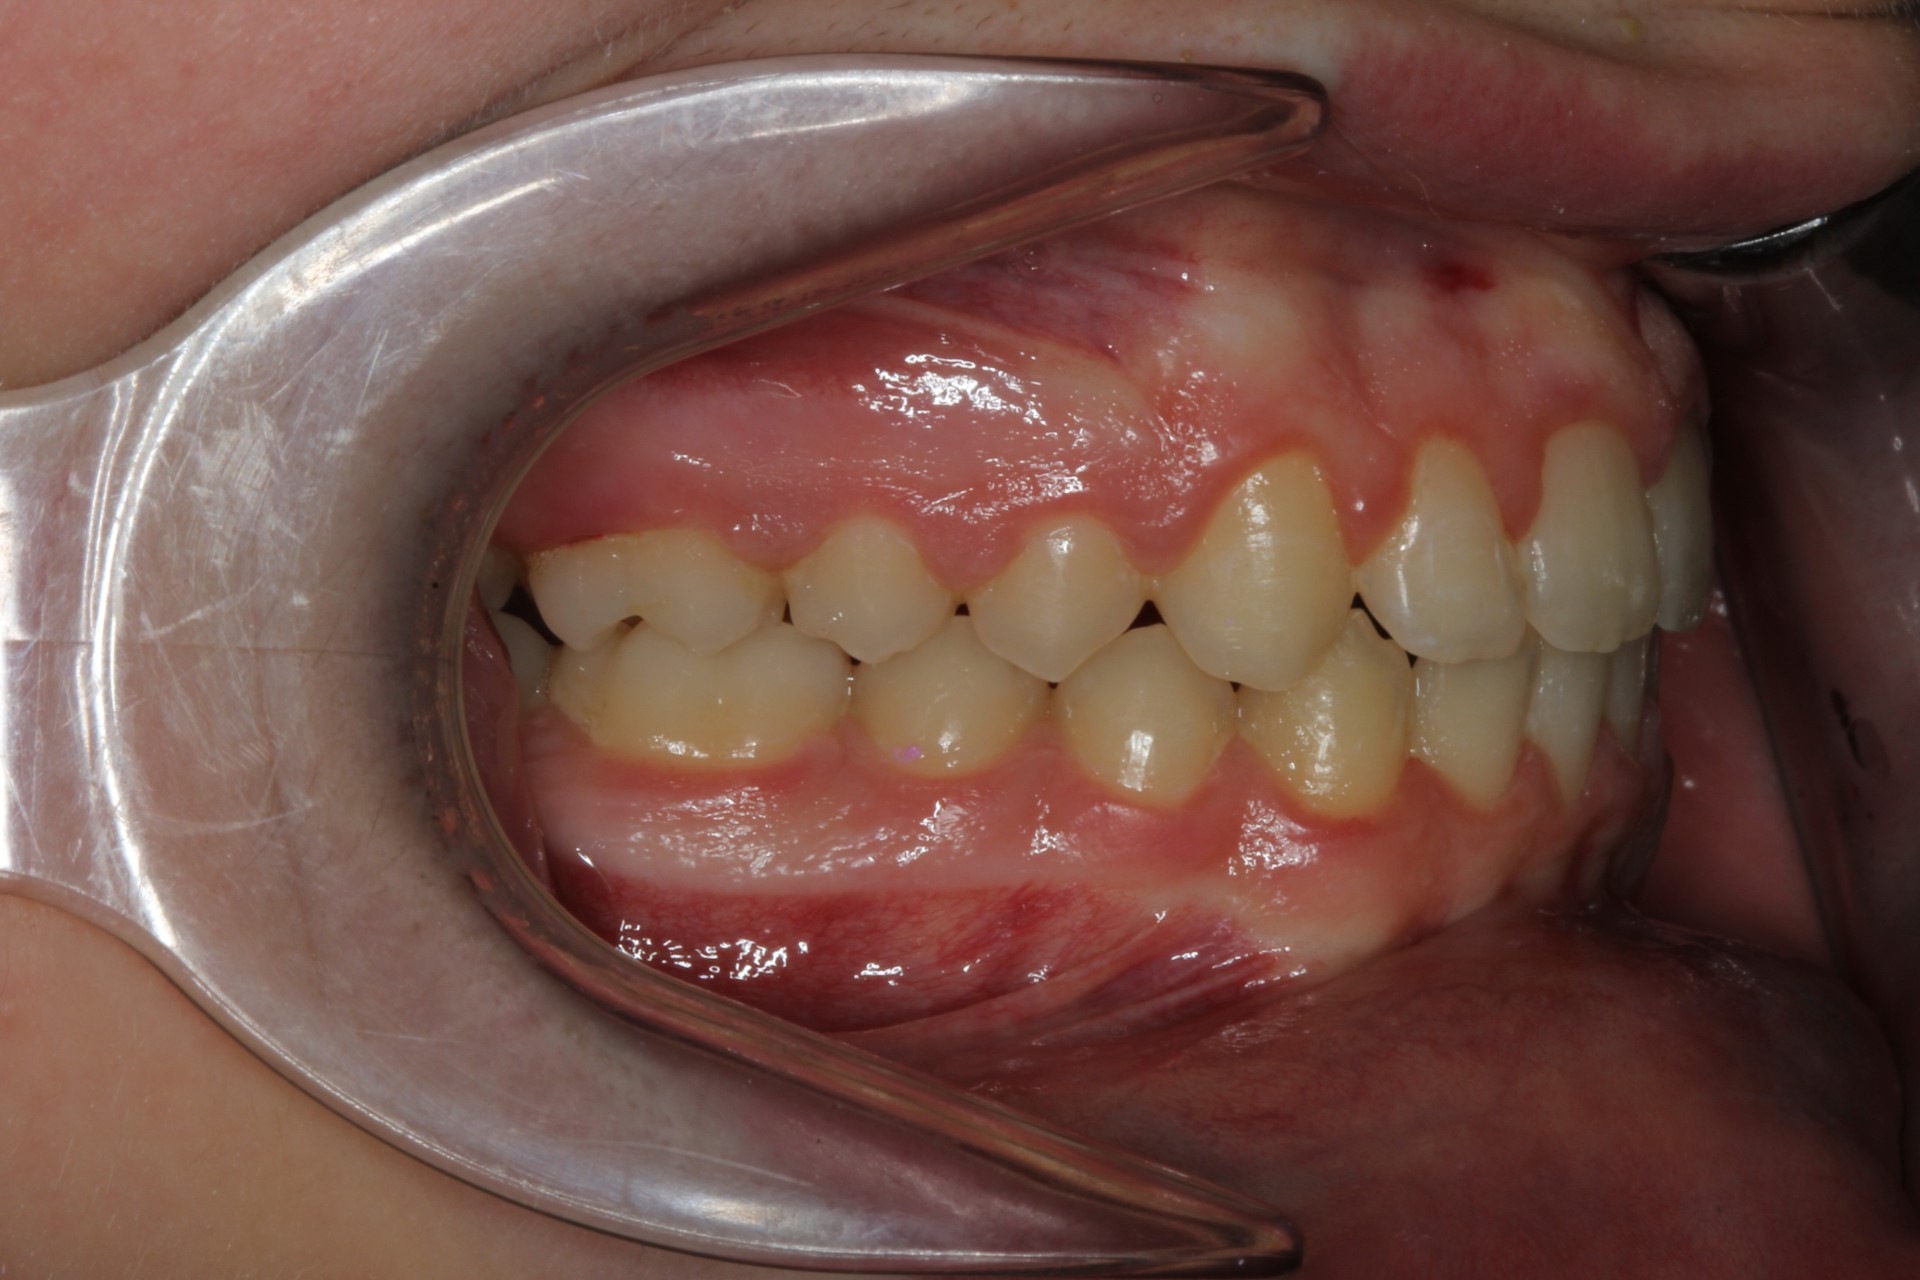

Crowding – Child case